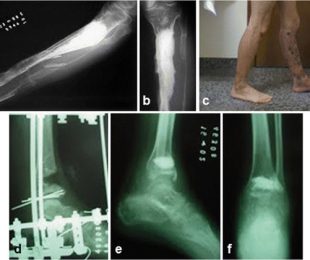

14- Fixação Externa nas Dismetrias dos Membros Inferiores

15- Pseudoartrose infectada

16- Pseudartrose umero= tratamento com a fixação externa de ILIzarov